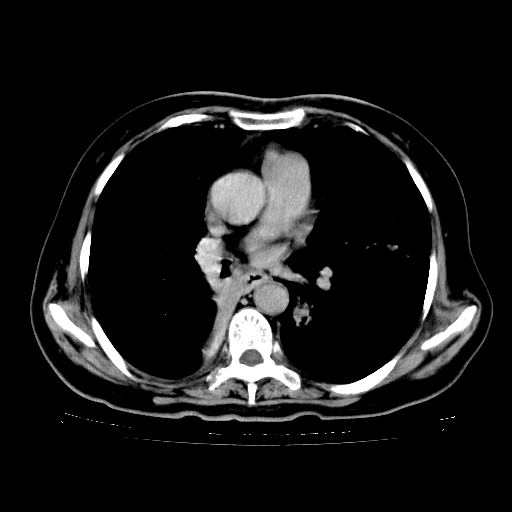

标题: CT23067:女,70岁,咳嗽、咳痰一个月,低热一周。 [打印本页]

女,70岁,咳嗽、咳痰一个月,低热一周。

1.左上肺结核,部分纤维化。右肺中下叶部分肺不张,内见液化、坏死及点状钙化,右中下叶支气管壁增厚、管腔狭窄,见多个点状钙化,结合临床考虑支气管内膜结核,建议痰检查抗酸杆菌并参考血沉。两肺多个小圆点状高密度灶,境界模糊,多考虑结核肺内播散。但本人年龄较大首先应支气管镜检以除外右肺癌。

2.胸主动脉夹层。

一元论:内膜结核伴下肺阻塞性肺炎并双肺播散!另:主动脉夹层。右侧少量胸腔积液。

继发型肺结核,右下肺支气管内膜结核.右侧少量胸腔积液.主动脉夹层.

支气管内膜结核肺内播散.右侧少量胸腔积液.主动脉夹层.